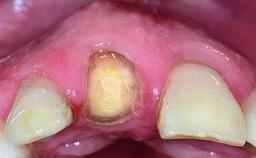

A 32-year-old female Caucasian patient with a compromised maxillary right central incisor was referred to us by a general dentist. Her chief complaints were discomfort and mobility of tooth 11 with unsatisfactory esthetics due to discoloration. The patient reported a previous trauma, some years earlier, as the origin of pathology on the afflicted tooth. Anamnesis was negative for any other dental or periodontal pathology in the remaining dentition. The patient did not take any medication and reported to be a light smoker (5–10 cigs/day). She had high esthetic expectations of her treatment. The extraoral examination revealed a high smile line with full exposure of her maxillary teeth and surrounding soft tissue in the area between the second premolars.

Lip Line No exposure of papillae Exposure of papillae Full exposure of mucosa margin

Periodontal Phenotype Low-scalloped, thick Medium-scalloped, medium-thick High-scalloped, thin

Soft Tissue Anatomy Intact Defective

Soft Tissue Contour and Volume Slightly compromised